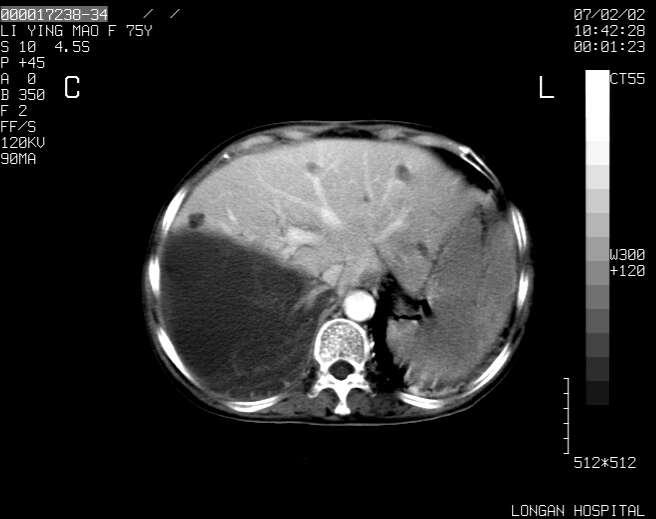

以下是引用dyqct在2007-2-10 8:53:00的发言:[br]考虑:1、肝脏多发囊肿[br] 2、左肾囊肿,右肾多发结石并积水。[br] 3、右胸少量积液。[br] 4、右肾周包裹性积液或淋巴管瘤(有见缝就钻的征象、薄隔、小结节状钙化)?[br] 5、腰椎动脉瘤样骨囊肿?[br] [br] [br]